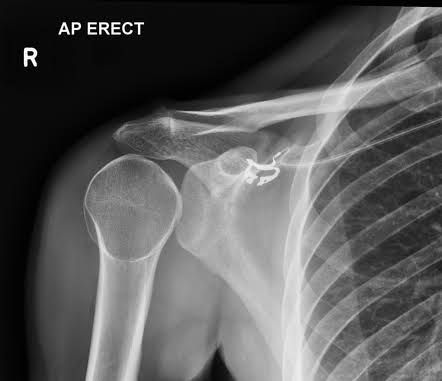

The light bulb sign refers to the abnormal AP radiograph appearance of the humeral head in posterior shoulder dislocation. When the humerus dislocates it also internally rotates such that the head contour projects like a light bulb when viewed from the front